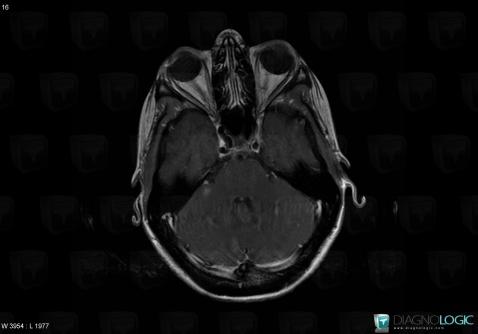

Toxoplasmosis, Posterior fossa, MRI

Here is the specific information in the key image above:

- Diagnosis Toxoplasmosis (link to Abscess), Location(s) Posterior fossa, with gamuts Infratentorial T2W or FLAIR hyperintense lesion